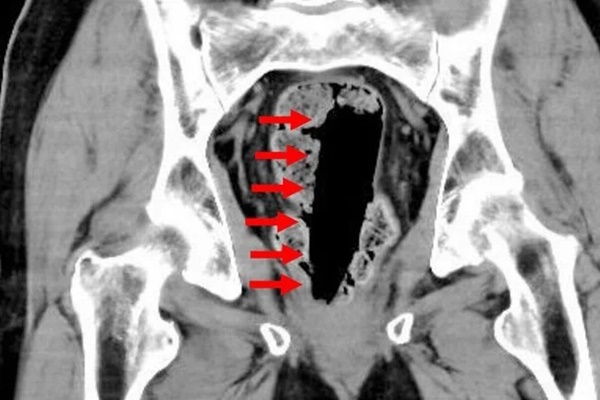

Kết quả chụp CT cho thấy, trong trực tràng có hộp đựng keo kích thước 35x35x120mm. Khi lấy nó ra, các bác sỹ nhận thấy vẫn còn nguyên chất keo lỏng bên trong hộp.

Kết quả chụp CT cho thấy một hộp keo ở phía trong hậu môn người bệnh. (Ảnh: Jam Press)